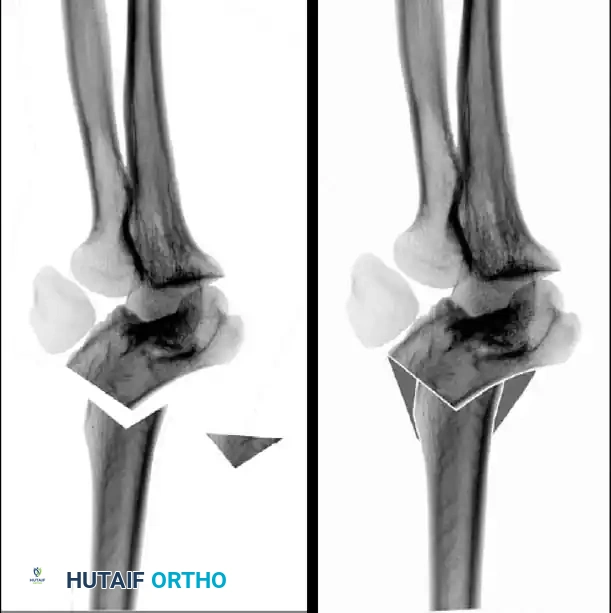

Fractures can present as angulated, translocated (shifted), or totally displaced. In the context of an elbow dislocation, the proximal fragment may become loose within the joint space or trapped, acting as a mechanical block to reduction.

Fig. 33-40 Examples of angulation, translocation, and total displacement of radial neck fractures.

The primary goal of treatment is to restore radiocapitellar alignment to preserve full pronation and supination.

Surgical Warning: Thirty to 45 degrees of residual angulation is generally accepted in closed treatment with satisfactory long-term functional results. Attempting open reduction for angulation less than 45 degrees may introduce unnecessary risks of stiffness, avascular necrosis (AVN), and radioulnar synostosis.